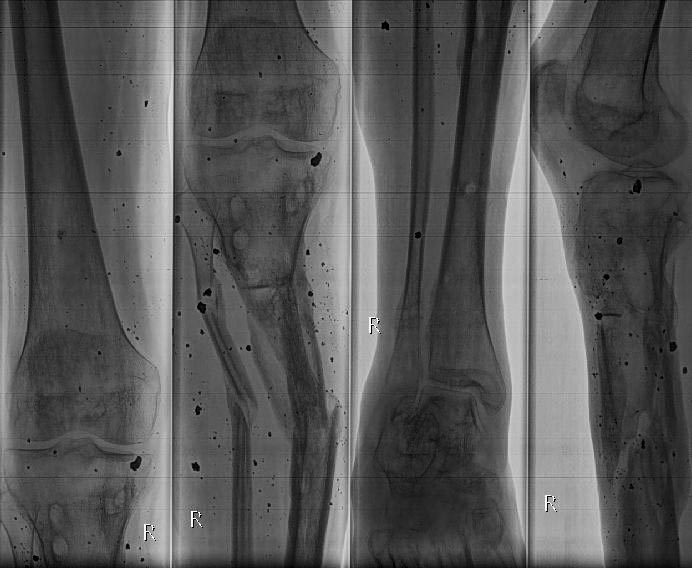

Деформации после минно-взрывного ранения.

Уважаемые коллеги, на лечении пациент 35 лет. 10 мес назад получил

травму, переломы велись в аппаратах. Сейчас ран нет. Снимки прилагаются.

Прошу высказать мнения о способах дальнейшего лечения. Спасибо.